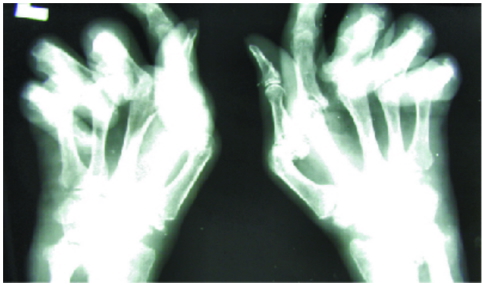

Rheumatoid Arthritis (RA)

- Symmetrical PIP joint synovitis (red, swollen, tender)

- Ulnar deviation

- MCP joint subluxation

- Z-deformity of thumb

- Swan neck and boutonnière deformities

- Small muscle wasting (thenar and hypothenar eminences)

- Palmar tendon crepitus